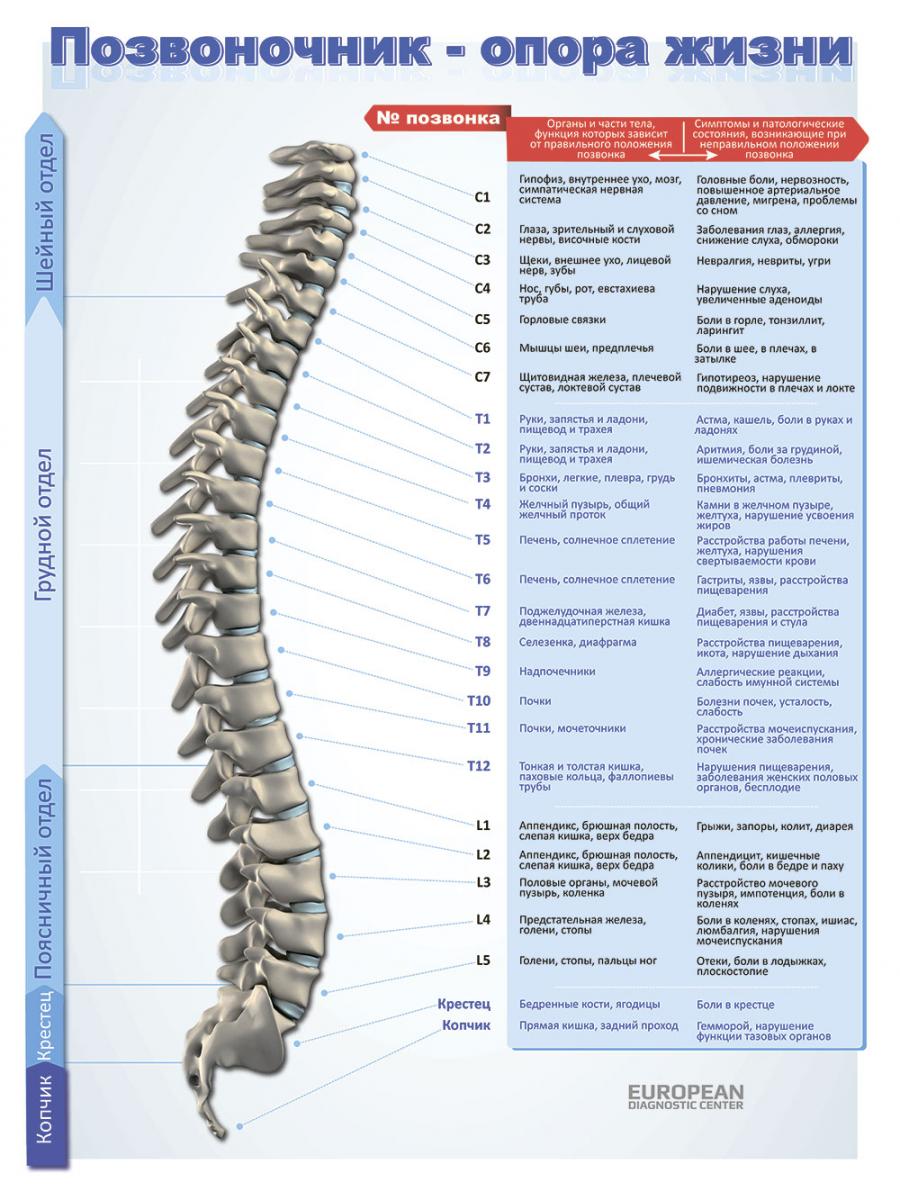

Отделы позвоночника для мрт схема фото и названия